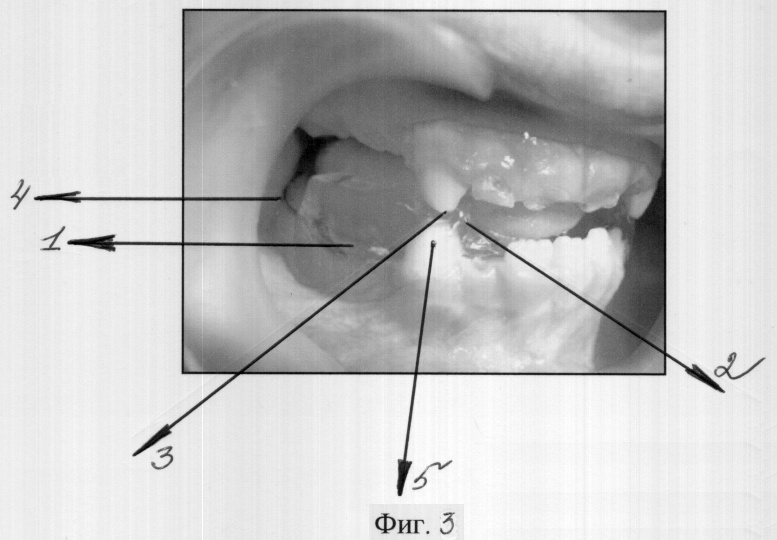

Сущность заявляемого изобретения поясняется фигурами 1, 2, на которых изображен общий вид заявляемого ортодонтического устройства, и фигурой 3, отражающей размещение предлагаемого устройства в полости рта.

Ортодонтическое устройство состоит из нижнечелюстной базисной пластинки 1 и окклюзионных накладок 2 с глубокими отпечатками зубов верхней челюсти в конструктивном прикусе 3. В дистальной части базисной пластинки 1 установлены опорно-удерживающие кламера 4.

Пациентам с синдромом «короткого лица», сопровождающимся патологиями – дистальная окклюзия или дизокклюзия, глубокая резцовая окклюзия или дизокклюзия, мезиальная окклюзия, с аномалиями, сопровождающимися дисфункцией ВНЧС, предварительно снимают оттиски с челюстей и отливают гипсовые модели. В лаборатории изготавливают восковые шаблоны для определения конструктивного прикуса. В следующее посещение определяется конструктивный прикус под контролем рентгеновского снимка ВНЧС. Рабочие модели гипсуют в артикуляторе. На рабочей модели с помощью крампонных щипцов изготавливают кламмера 3. Базисным воском моделируют базисную пластинку 1, окклюзионные накладки 2 на нижние клыки 5 с отпечатками верхних зубов 3 в артикуляторе. В последующем воск заменяют базисной пластмассой.

Пациенту было предложено провести разобщение и удержание челюстей в конструктивном прикусе. Для этого было изготовлено и установлено заявляемое ортодонтическое устройство на нижней челюсти пациента К. (см. Фиг.2).